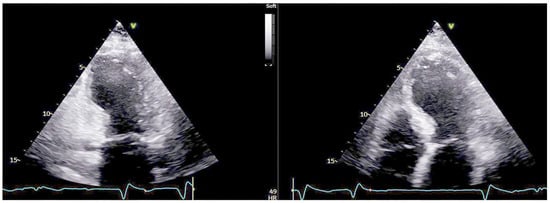

Recurrent Takotsubo Syndrome with Contemporary Brady- and Tachyarrhythmic Presentation

Case Description